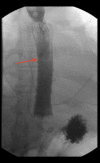

BACKGROUND Pulmonary vein isolation is a method of cardiac ablation therapy used to treat irregular heart rhythm, including atrial fibrillation (AF). This report presents a case of esophagopericardial fistula (EPF) and pneumopericardium as a complication of pulmonary vein isolation in a 62-year-old man with AF. CASE REPORT We report the rare case of a 62-year-old man with a medical history of persistent atrial fibrillation status after ablation 3 days prior to his initial Emergency Department visit for chest pain. Acute coronary syndrome was ruled out with normal electrocardiogram, echocardiography, and troponin tests. Fluid overload and sotalol adverse effects were presumed to be the cause of his symptoms. We discontinued sotalol with diuresis and he was discharged home when his chest pain subsided. Nine days later, he returned to the Emergency Department with worsening similar symptoms and was eventually diagnosed with EPF and pneumopericardium on a computed tomography scan of the chest with contrast. He was managed with esophagogastroduodenoscopy and stent placement along with subxiphoid pericardial window and pericardial drain placement. The patient was discharged in stable condition after removing the pericardial drain. At 10-day and 1-month follow-up, he had no recurrent symptoms. CONCLUSIONS This report shows that although EPF with pneumopericardium is a rare complication of pulmonary vein isolation, it should be rapidly diagnosed and treated as a life-threatening emergency.